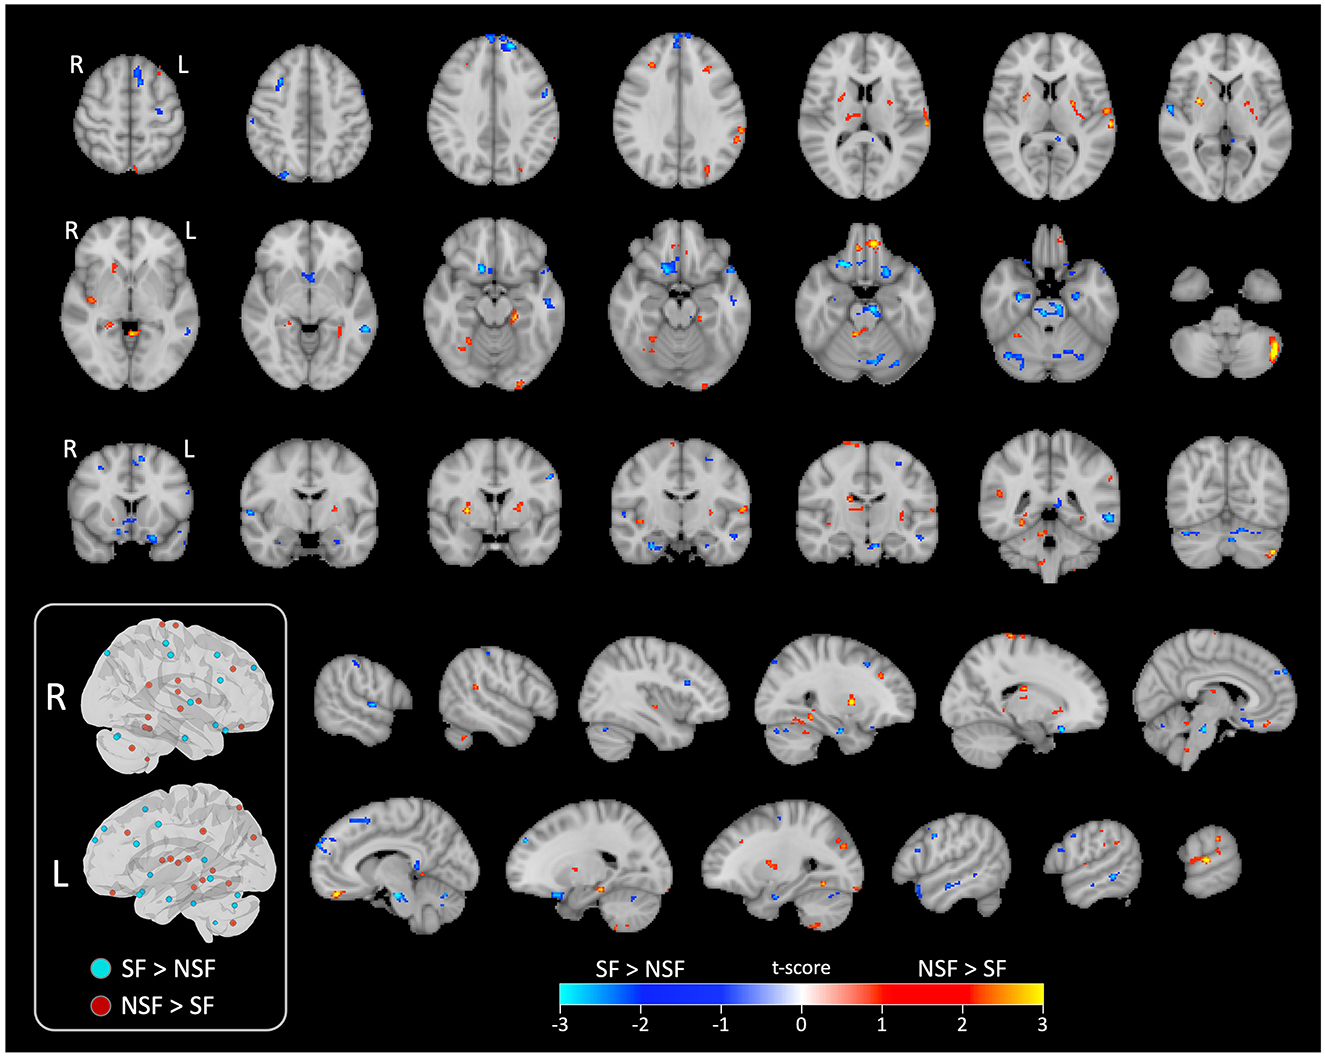

The GLM analysis, adjusted to clinical data, yielded 24 significant clusters indicating higher brain ICA-derived FC patterns in the SF group than in the NSF group; and 34 significant clusters with higher FC pattern in the NSF group. The involved AAL brain regions of each cluster, cluster sizes, and the coordinates of the maximum t-score are listed in Supplementary Table S1. The major brain regions involved in clusters were visually assessed (Figures 3, 4) and summarized in Table 2.

Brain surface renderings showing functional MRI data in both ipsilateral and contralateral views. Color mapping indicates t-scores, with blue for SF greater than NSF and red-yellow for NSF greater than SF, ranging from -3.0 to 3.0.

Figure 3. Significant clusters displayed on smoothed cerebral surface. L, left/ipsilateral; R, right/contralateral; SF, seizure free; NSF, not seizure free.

Rows of brain MRI scans display different brain slices with color-coded areas indicating t-scores. A legend shows blue for SF greater than NSF and red for NSF greater than SF. The images highlight differences in brain activity.

Figure 4. Significant clusters displayed on series of image slices. Schematic visualization of the significant clusters in 3D brain views (inside the box). All clusters that were ipsilateral to the side of TLE are shown in the left view, while contralateral clusters are shown in the right view. L, left/ipsilateral; R, right/contralateral; SF, seizure free; NSF, not seizure free.

In temporal lobe, the SF group had greater ICA-derived FC patterns in the bilateral anterior PHG, bilateral anterior superior temporal gyrus, and the ipsilateral middle temporal gyrus. In contrast, the NSF group exhibited greater FC patterns in the posterior and basal temporal lobe extending to the fusiform gyrus bilaterally and the ipsilateral middle occipital gyrus.

In frontal lobe, there was greater FC pattern in the bilateral basal and mesial frontal regions, including the posterior orbitofrontal cortex (OFC). The NSF group, by comparison, demonstrated greater FC pattern in the bilateral anterior OFC and contralateral supplementary motor area (SMA) and precentral gyrus (Figure 3).

Within cerebellum, both the SF and NSF groups exhibited brain FC pattern in the posterior cerebellum bilaterally. However, the NSF group had a larger network distribution, including the contralateral anterior cerebellum (Figure 4). In subcortical and insular regions, the NSF group exhibited greater FC patterns in the bilateral insula, bilateral putamen, contralateral caudate and contralateral thalamus, whereas the SF group showed stronger FC expression in the brainstem (pons; Figure 4).

Overall, SF group demonstrated more localized FC patterns, primarily in ipsilateral mesial temporal and frontal regions, whereas NSF group showed more diffuse and contralateral FC, involving temporal, frontal, insular, subcortical and cerebellar regions (Table 2).